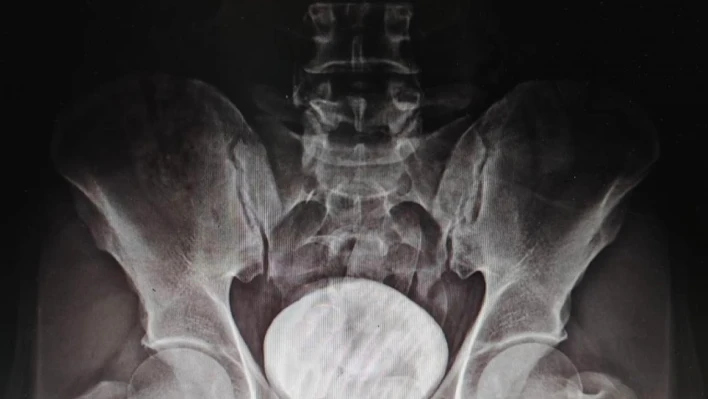

Polis yaptığı üst aramasında bir şey bulamayınca şüpheliyi Kars Harakani Devlet Hastanesine götürdü. Burada çekilen röntgen sonucu Mohammad Zadeh Tazehkand’ın mide ve bağırsaklarında kapsüller içerisinde 7 parça halinde 258,53 gram metamfetamin maddesi tespit etti.